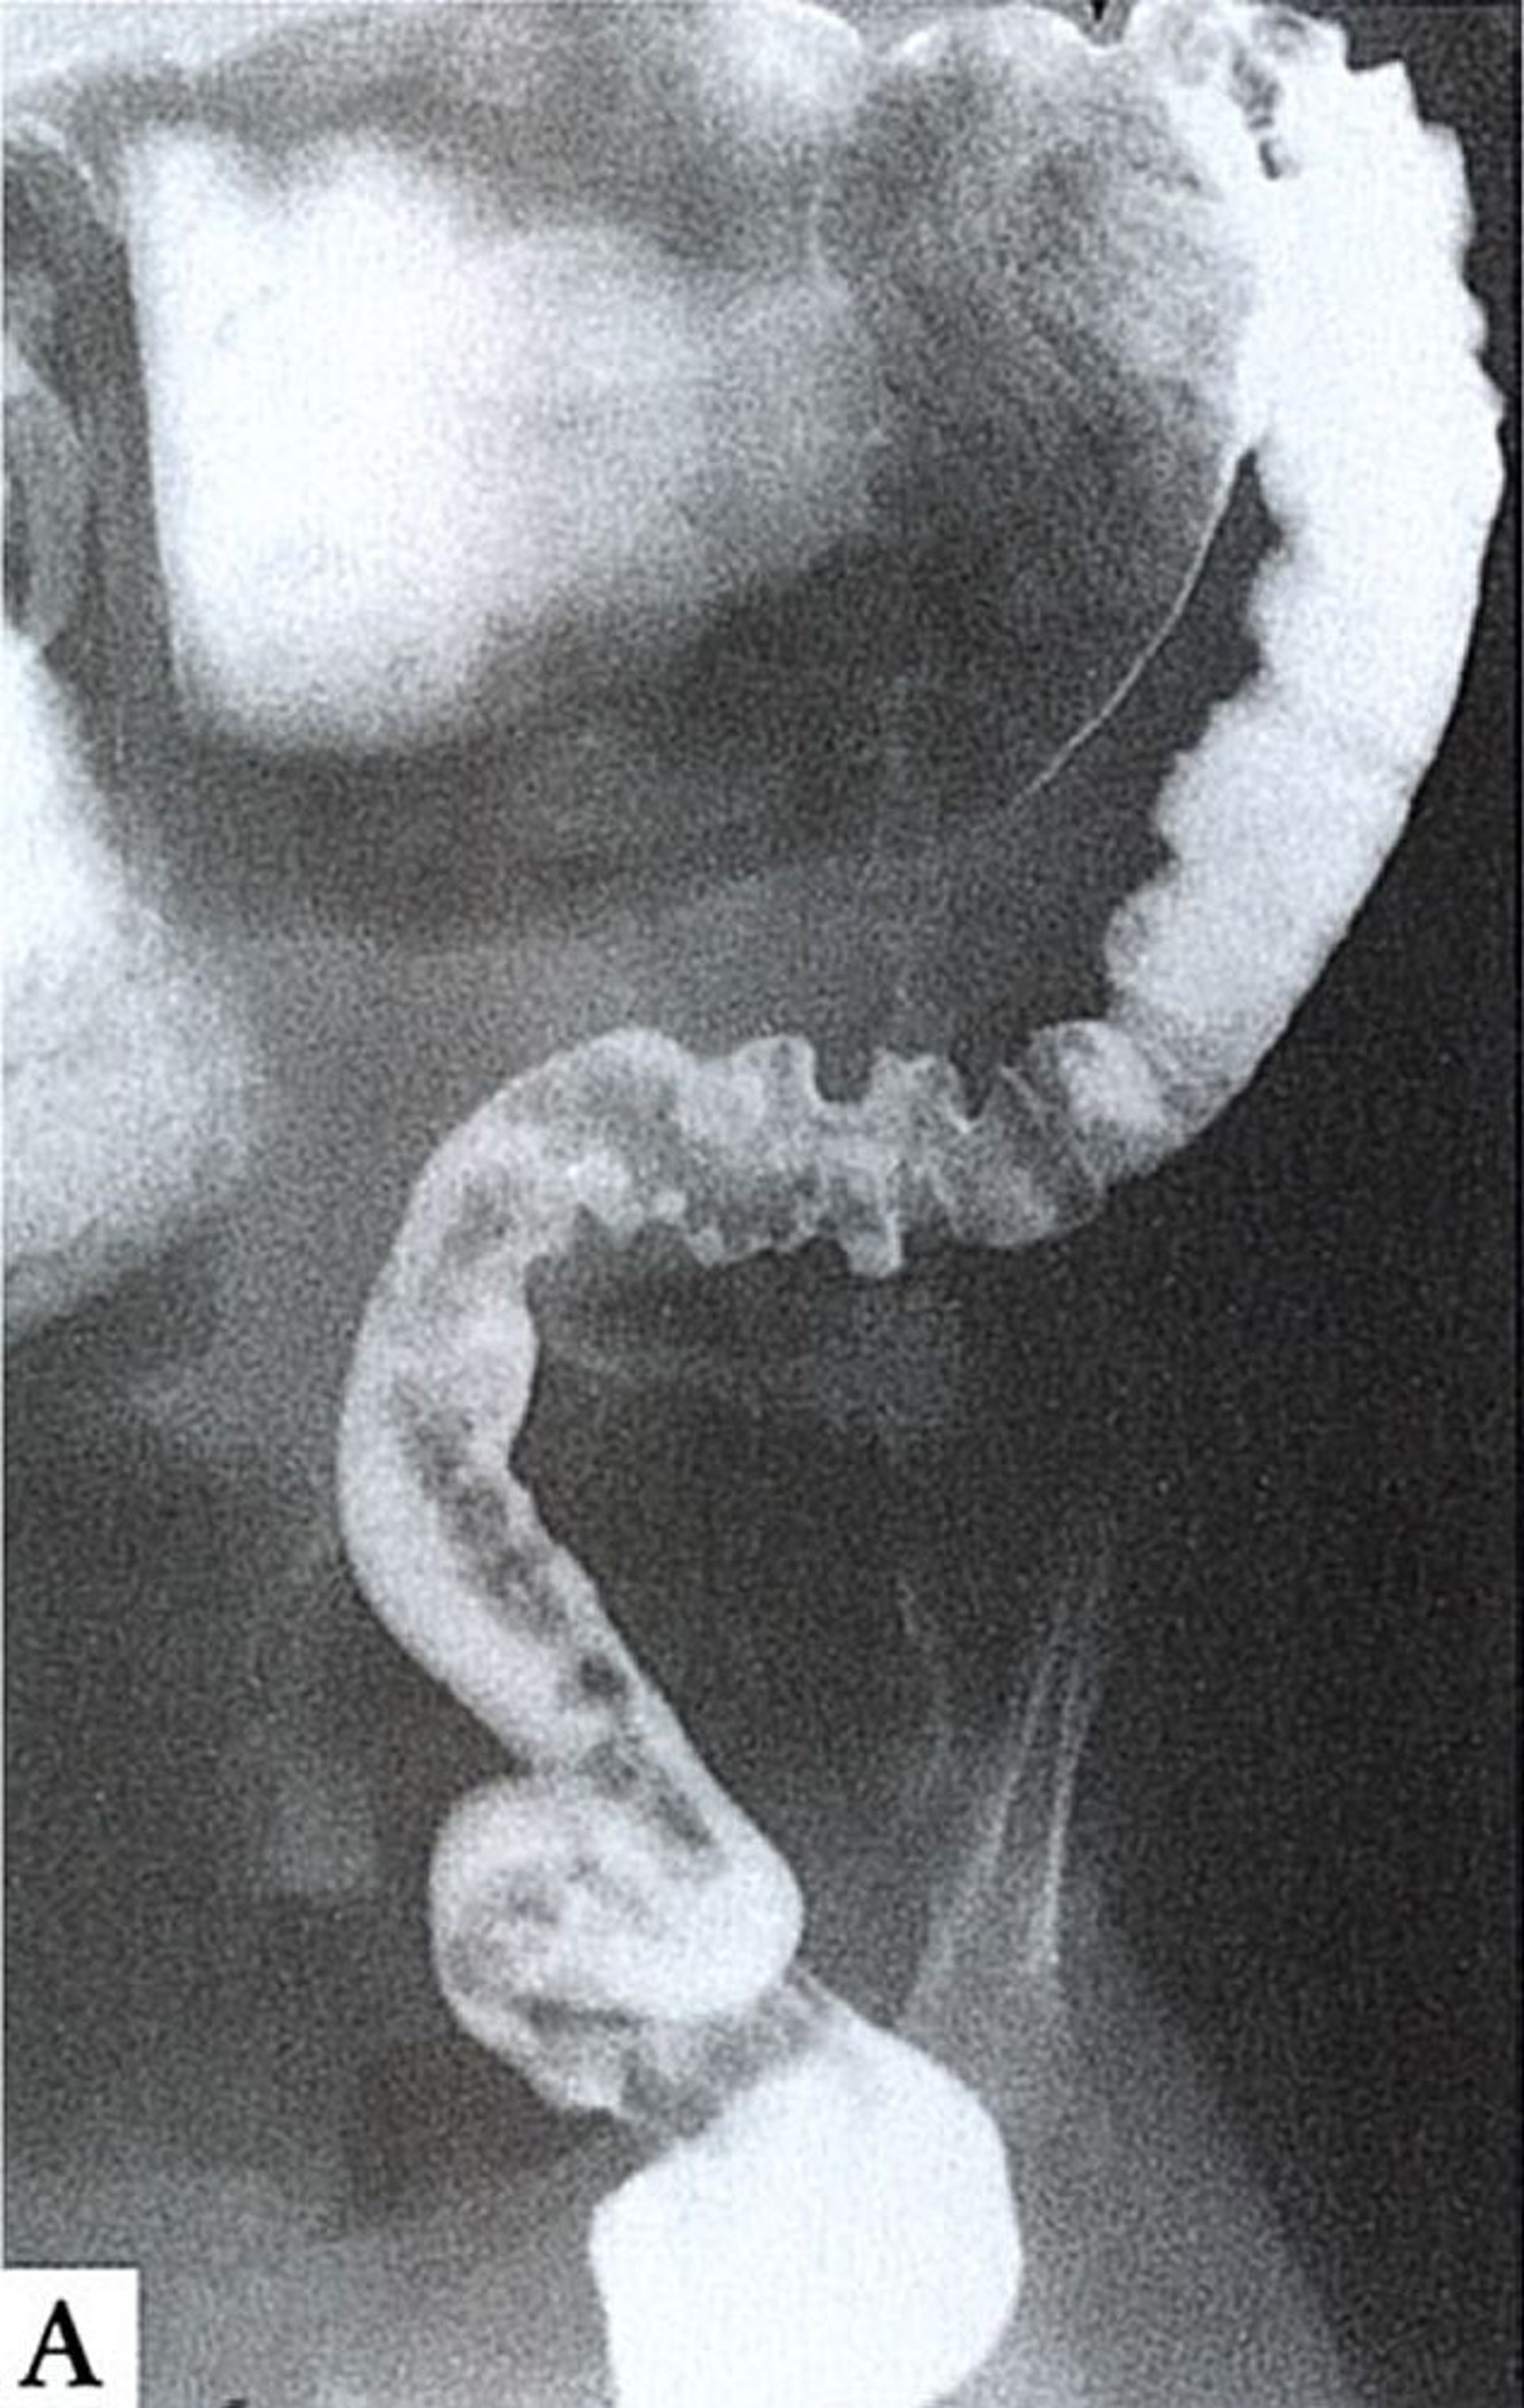

This barium enema shows aganglionosis up to the splenic flexure. The aganglionic bowel is narrowed and spastic (right), whereas the normally innervated proximal bowel (top) is dilated and filled with fecal material.

By permission of the publisher. From Wald A: Gastroenterology and Hepatology: Colon, Rectum, and Anus. Edited by M Feldman (series editor) and CR Boland. Philadelphia, Current Medicine, 1996.